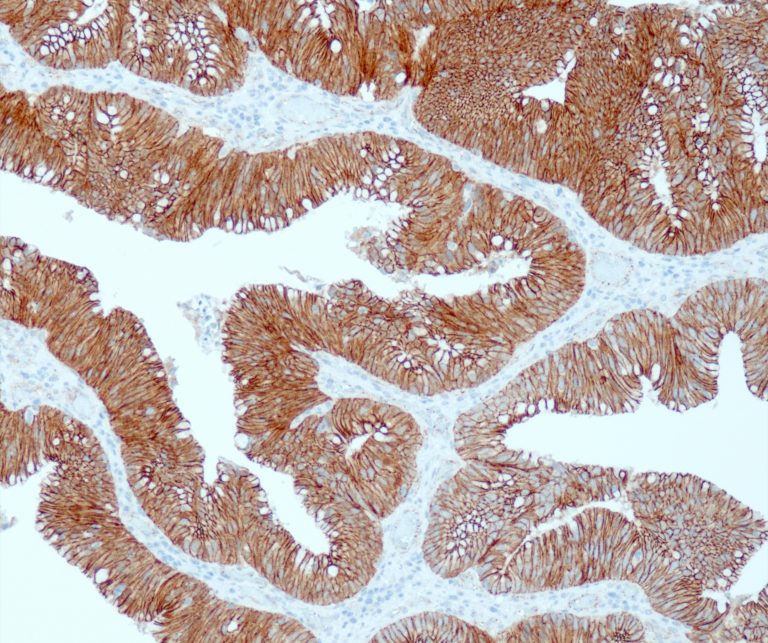

Gastrointestinal (GI) Pathology

General Marker